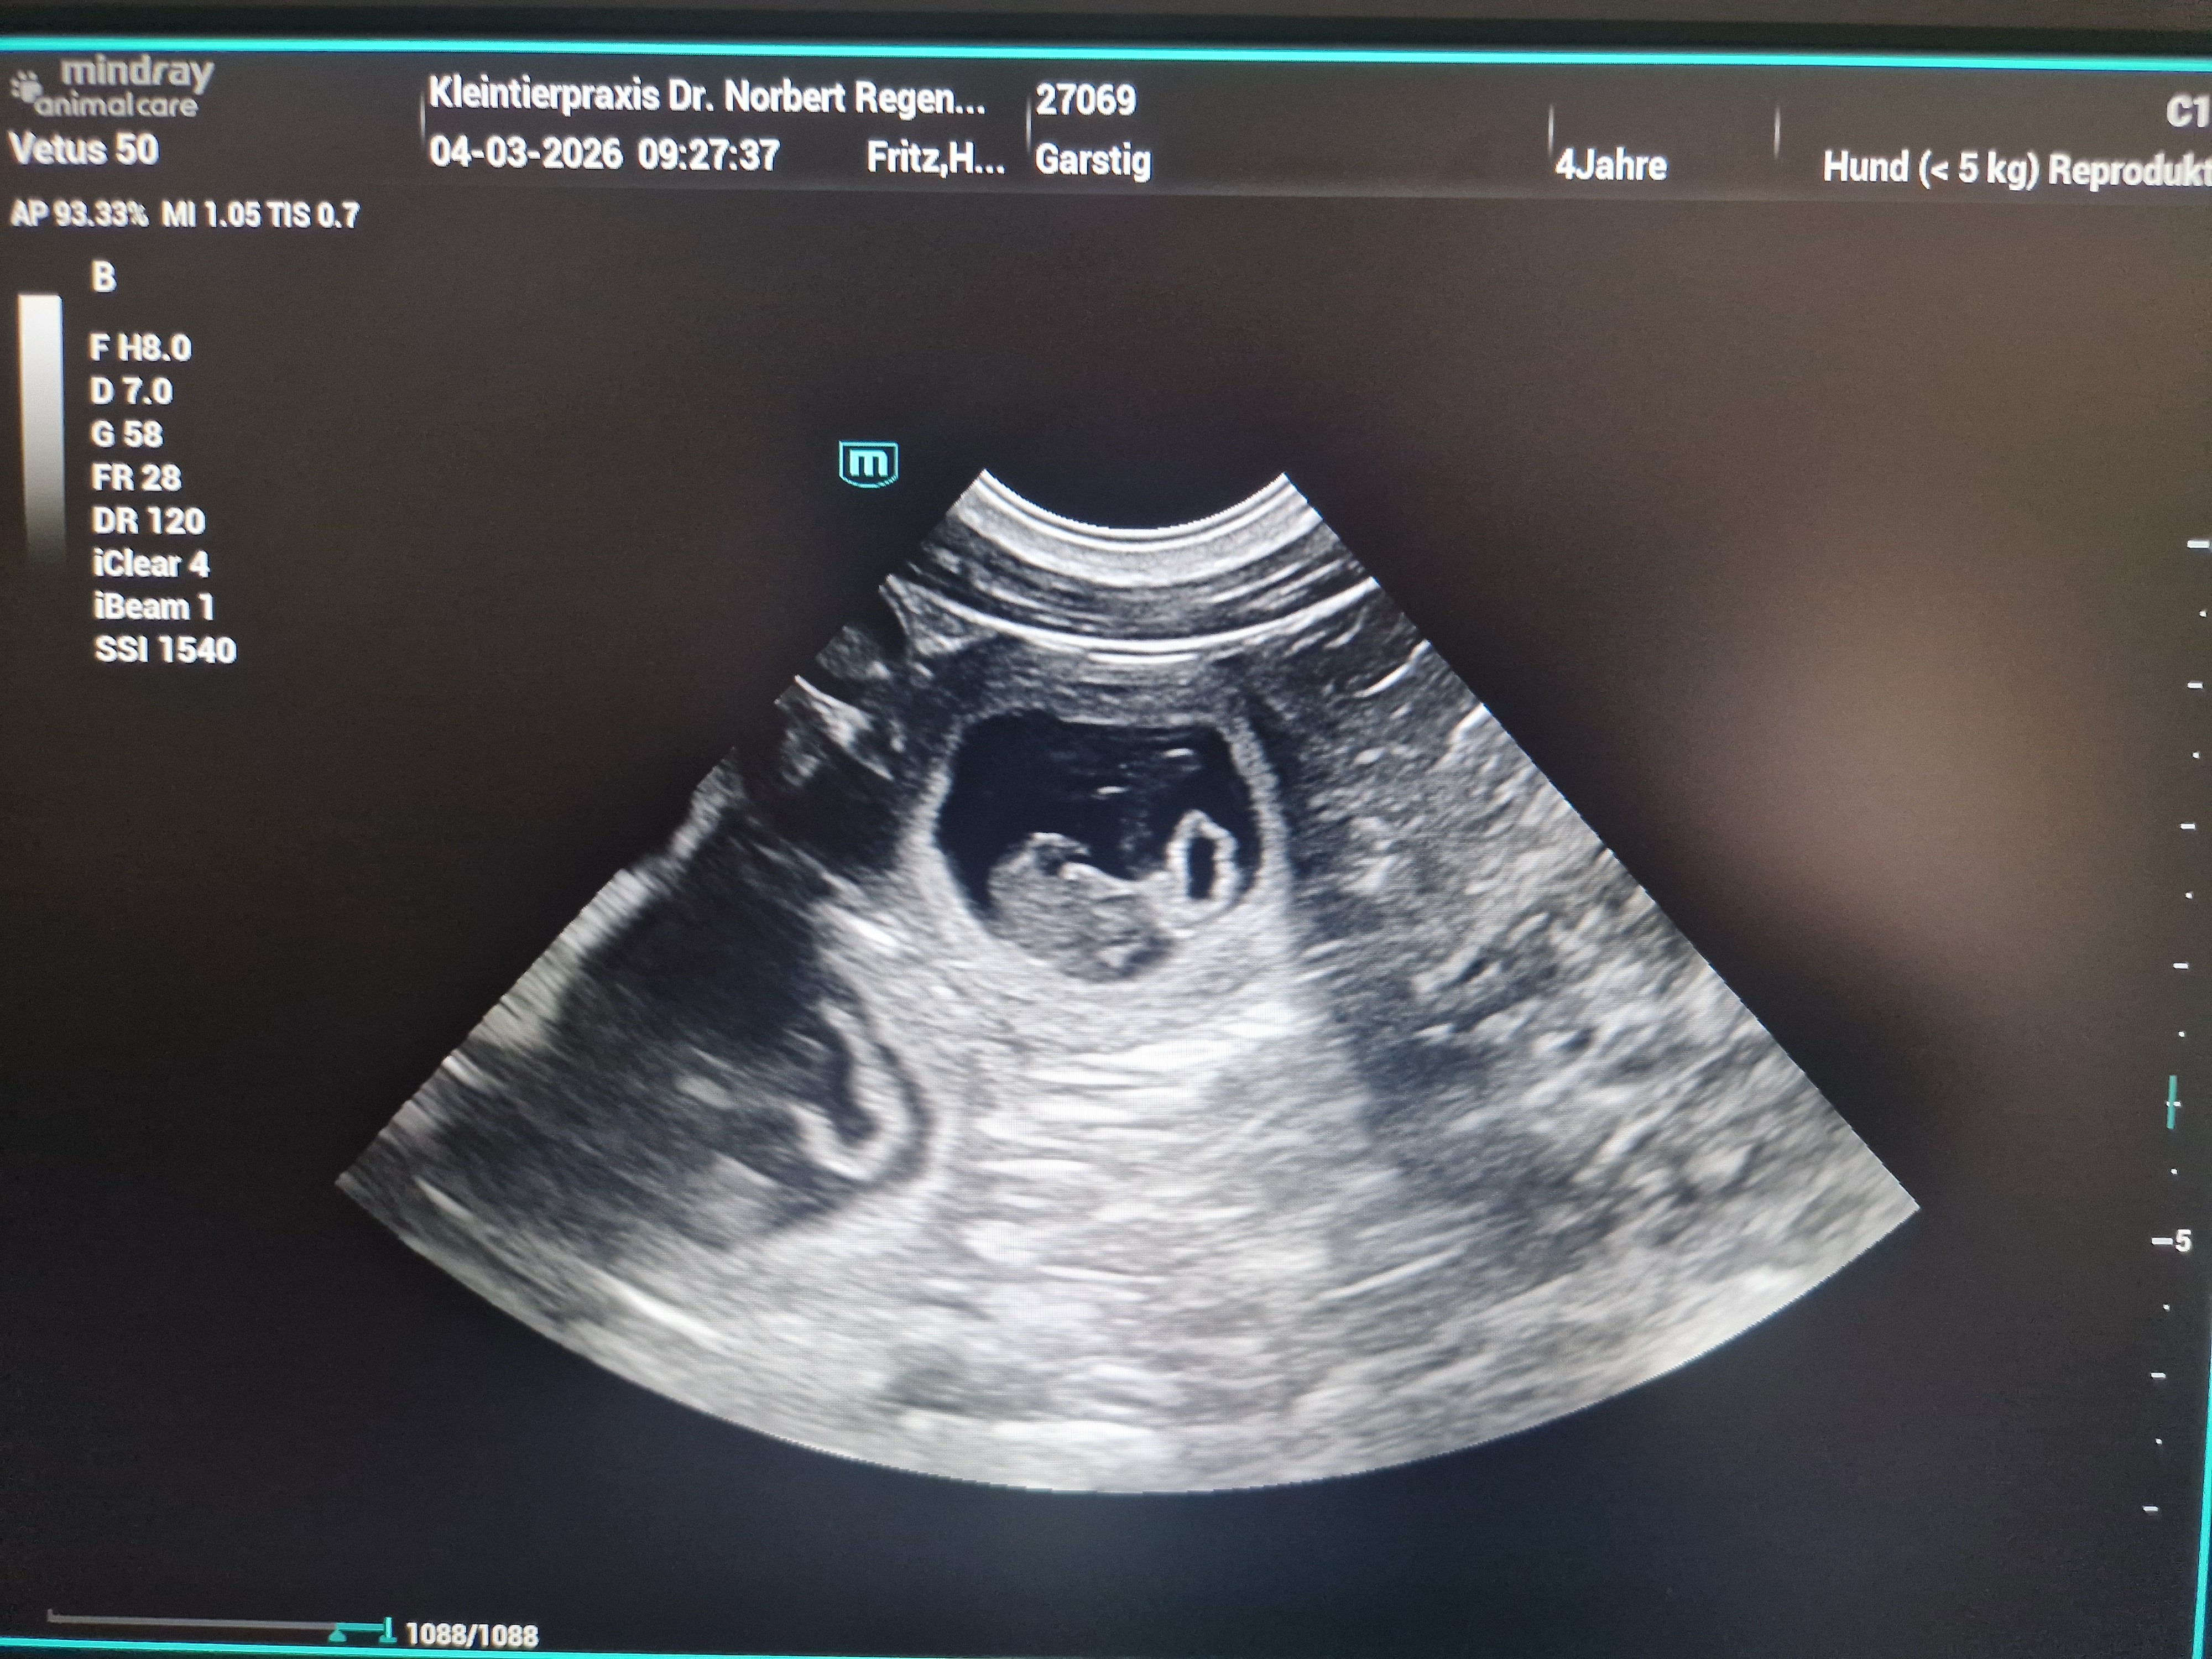

(04.03.2026) Yeaahhhh! Wir sind "schwanger"!

Heute haben wir es schwarz auf weiß und auch ein wenig bunt bekommen:

Garstig ist trächtig!!!

Der Tierarzt konnte 6 - 8 Welpen schallen, aber wie viele Welpen genau "drin" sind, werden wir erst erfahren, wenn sie ausziehen!

Beim Ultraschall ist es immer schwierig, da die Fruchthüllen ständig etwas hin- und herwabern. Und da ich meine Hündin nicht röntgen werde, müssen wir bis zum Auszug warten! :-)